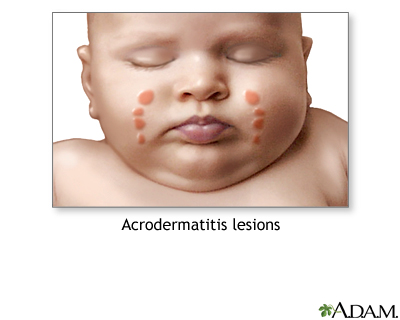

- Childhood illnesses such as chickenpox, measles, roseola, rubella, hand-foot-mouth disease, fifth disease, and scarlet fever.